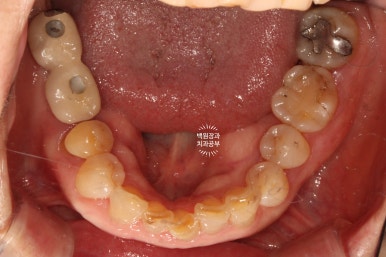

교합면에서 보았을 때 제작해드렸던 임플란트 크라운도 깔끔하게 잘 관리하고 계셨습니다.

이렇게 잘 쓰고 계신 모습을 보면 정말정말로 치과의사로써 큰 보람을 느낍니다 :)

3년이 지나니 상악동 뼈이식술을 했던 곳은 이제 거의 내 뼈와 하나가 된 것처럼 예쁘게 성숙된 모습을 보여주고 있고, 앞니 지르코니아 크라운은 꼼꼼히 관리해주신 덕분에 충치 하나 없이 신경치료 하지 않았음에도 아주 잘~ 쓰고 있는 모습을 확인할 수 있었습니다!